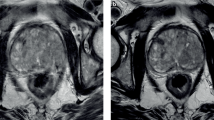

The details of the study population are shown in Table 1. Median patient age was 68 years (IQR: 63–72), and median PSA was 6.8 ng/mL (IQR: 4.9–9.3 ng/mL). Most MRIs were performed in patients with an elevated PSA and negative prior biopsy(-ies) [42% (105/249)] or in those with low-risk prostate cancer being considered for active surveillance [36% (89/249)] (Table 1, Fig. 1). Image quality was significantly (p < 0.001) more likely to be impaired or non-diagnostic in the first three months (Fig. 2). Seven examinations [3% (7/249); 6 in months 1–6, 1 in months 7–12] were not assigned a PI-RADS v2 score because they were performed following local therapy (Table 1).